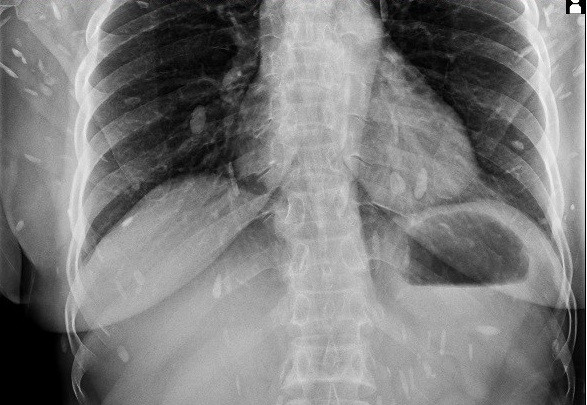

Hình ảnh về sán lá gan xâm nhập cơ thể của bà Đ. (ảnh bệnh viện cung cấp)